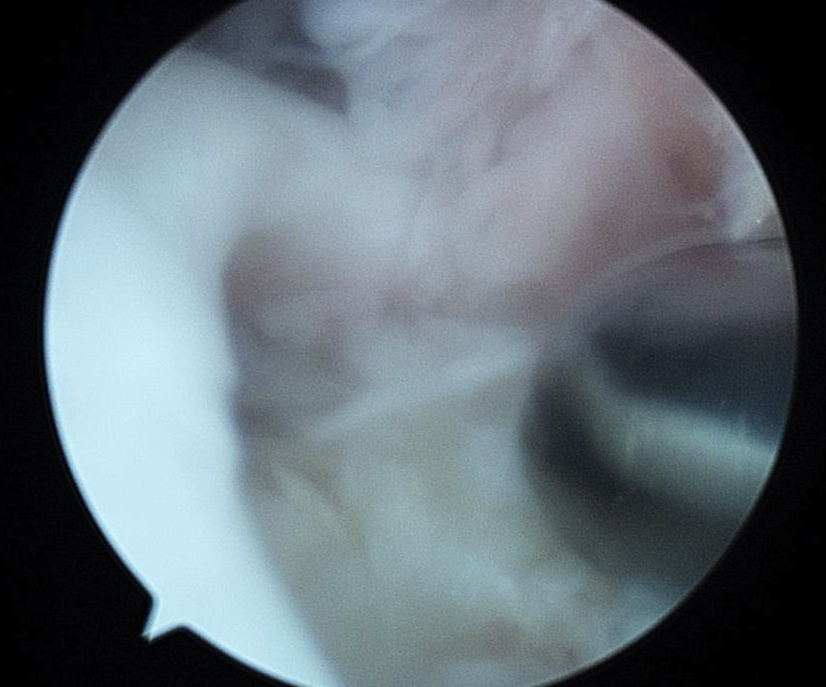

Subacromial joint

- bursectomy for visualization

- acromioplasty if acromial spur

- debride footprint to bleeding bone

- +/- microfracture / K wire of footprint / marrow stimulation

Assess tear

- large tears may need releases

- consider margin convergence sutures for large U shaped tears

Margin convergence sutures

Medial row anchors

- inserted through additional stab incision for suture management

- just medial to articular cartilage

Pass sutures through medial cuff tendon

- camera posterior

- suture passer via lateral portal

- retrieve sutures through anterior portal

- repeat

- tie medial row

Double row / suture bridge

- use medial row sutures

- secure in knotless lateral row anchors